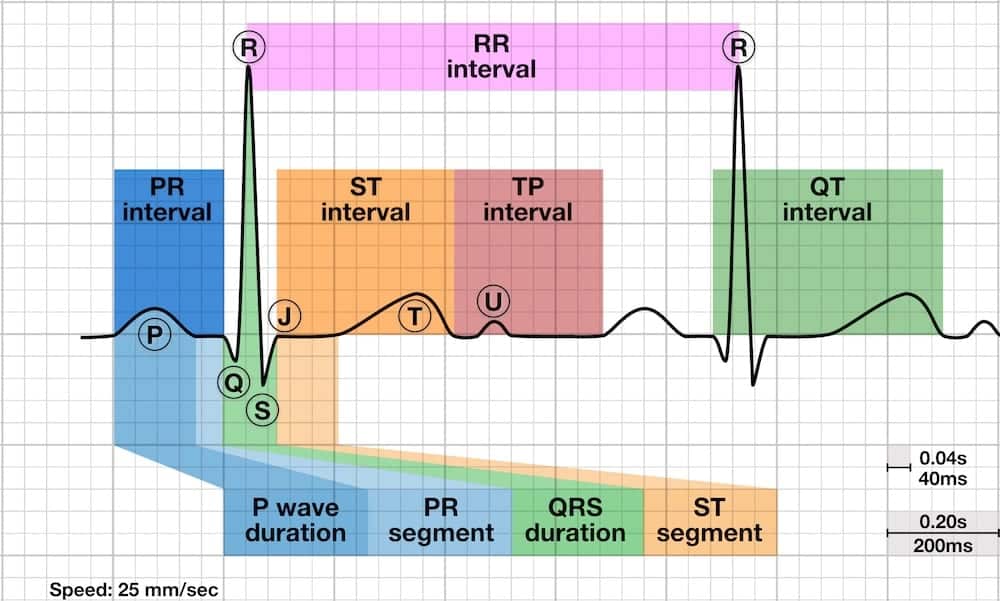

ECG Example – U Wave

Note that there is a positive deflection (arrowed) after the T wave, and before the next P wave, that is the U wave.

© Life in the Fast Lane. Licensed under CC BY-NC 4.0